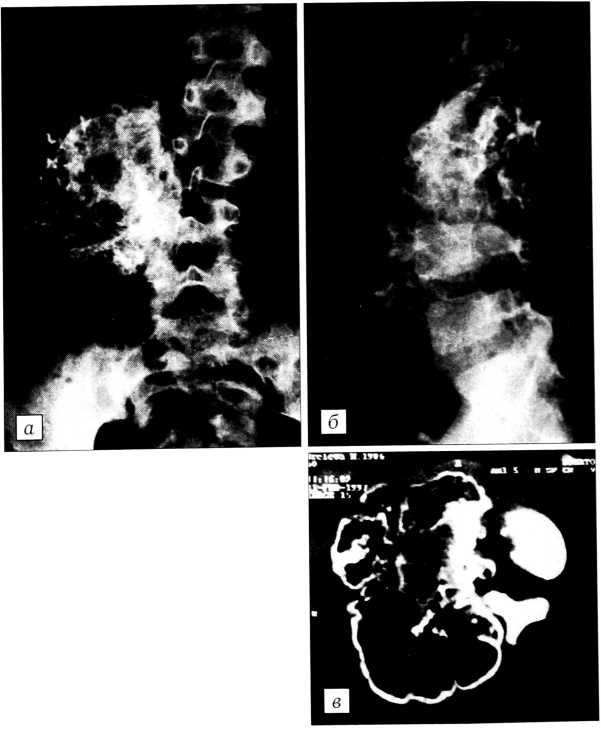

Невринома, нейрофиброма. Эти вторичные поражения позвоночника встречаются редко (3,4%), являются не костными новообразованиями, а ис-

ходят из оболочек нервных стволов или наружного слоя надкостницы дуг либо отростков [11, 48]. Опухоли могут достигать больших размеров и сдавливать содержимое позвоночного канала, чаще локализуются в области крестца и вызывают значительное разрушение костной ткани. Дифференцировать приходится прежде всего с хрящевыми опухолями и ГКО. Лечение: удаление опухоли; при необходимости — стабилизация позвоночника и костная пластика (рис. 2,3).

Рис. 2. Больной С. 19 лет. Диагноз: нейрогенная опухоль. На ангиограмме (а) — смещение подвздошных сосудов, на урограмме (б) — сдавление мочевого пузыря и мочеточника, на КТ (в) — мягкотканная опухоль занимает весь малый таз. Гистологическое исследование: злокачественная нейрофиброма.

Рис. 3. Больная С. 51 года. Диагноз: нейрогенная опухоль крестца. На МРТ (а) деструкция крестца с наличием экстравертебрального компонента и сдавлением дурального мешка. Оперирована в два этапа: 1) субтотальное удаление опухоли, спондилодез фиксатором «Медбиотех»; 2) удаление всей опухоли реберно-паховым доступом (б). Гистологическое исследование: нейрофиброма.